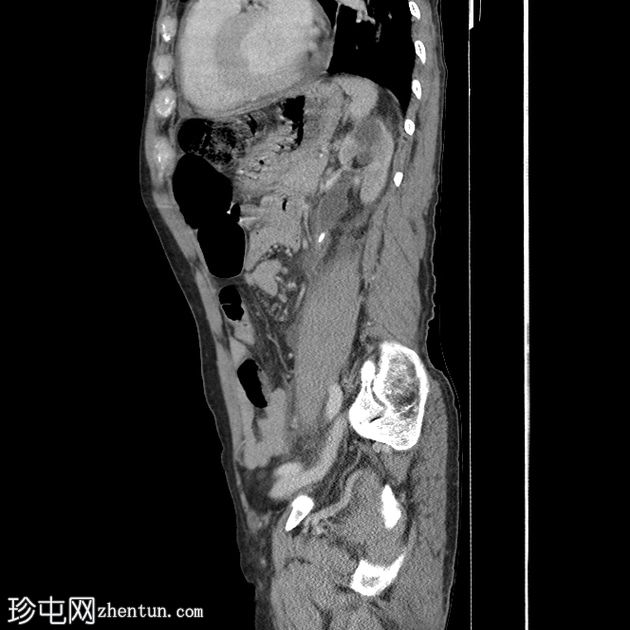

矢状位增强扫描(门静脉期)

门静脉期(冠状位、矢状位)可见左侧肾周间隙少量积液,液体沿左侧髂腰肌向下走行。延迟期可见造影剂外渗至左侧肾周间隙,提示尿囊肿。

左侧近端输尿管结石导致中度肾积水,结石大小为0.8 x 0.6 cm,左肾可见一微小非梗阻性结石。

影像学上,尿瘤通常表现为肾周或腹膜后间隙的液体积聚。在本例中,延迟 CT 扫描清晰地显示造影剂从(肾盏/肾盂/输尿管)渗出并积聚在肾周间隙,证实了尿瘤的存在。